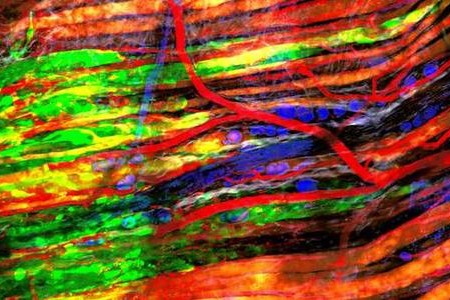

L’intuizione alla base dello studio è che le cellule tumorali, a causa della loro velocità di crescita e delle specifiche alterazioni metaboliche che le caratterizzano, siano strettamente dipendenti dal metabolismo degli acidi grassi per produrre, tra l’altro, le membrane delle cellule figlie.

Peluso e Montanaro assieme ai loro collaboratori e ai ricercatori della Sigma-Tau hanno dimostrato che utilizzando un farmaco sperimentale, denominato ST1326, si riesce ad inibire il sistema della carnitina acil-transferasi. Tale sistema è necessario per il trasporto degli acidi grassi all’interno del mitocondrio – la centrale energetica della cellula – dove avviene il loro metabolismo.

“In questo modo, vengono compromessi la produzione e il mantenimento delle riserve cellulari di una molecola, l’acetato, indispensabile per generare nuovi lipidi, costituenti essenziali delle membrane cellulari”, spiegano Peluso e Montanaro. “Il farmaco ha dimostrato di avere un effetto tossico selettivo, colpendo preferenzialmente le cellule tumorali. Rispetto alle cellule sane, quelle neoplastiche risultano essere infatti molto più sensibili al farmaco, accumulano nel citoplasma i lipidi che non vengono metabolizzati e non sono in grado di generarne di nuovi e quindi di proliferare”.